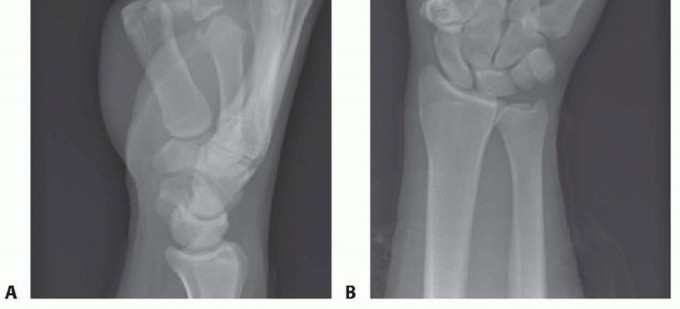

FIG 2 • X-rays showing MP joint dislocation on AP (A) and lateral (B) films. (continued)